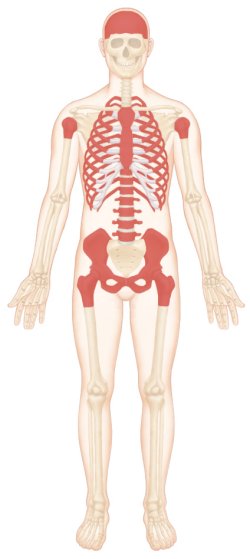

다양한 원인에 의해 골수세포의 기능과 세포충실성(cellularity)이 감소하고 골수조직이 지방으로 대체되면서, 적혈구, 백혈구, 혈소판 모두가 감소하는 범혈구 감소증(pancytopenia)이 나타나는 조혈 기능의 장애를 나타내는 질환이다.

전형적인 골수소견은 조혈모세포(stem cell; 모든 종류의 혈액세포를 만들어낼 수 있는 능력을 가진 세포)의 감소와 함께 텅 빈 골수가 지방으로 차 있다.

- 조혈세포조직 감소

- 골수세포충실도의 감소

- 지방조직으로 대체